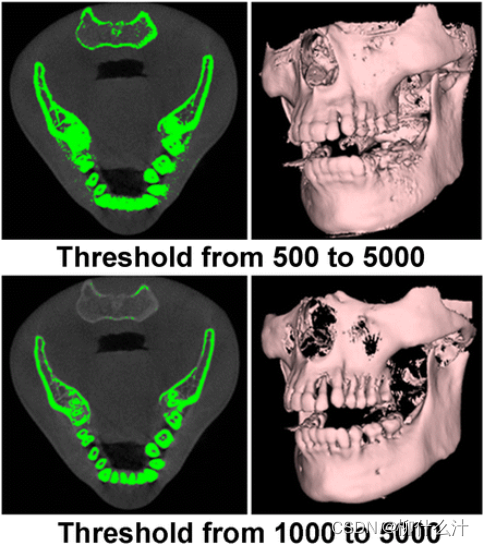

除了二维切片,还有三维渲染。可以对表面渲染和体积渲染进行区分。表面渲染(也成为间接体积渲染)是一种将图像数据转化为几何基元并进行渲染的技术,因此可能会出现一些信息的损失,因为它只显示阈值区域的表面。

用不同的阈值进行表面渲染。一个“从x到y的阈值”意味着只有x和y之间的灰度值可以保留用于可视化

第二张图是不同阈值进行的体积渲染。